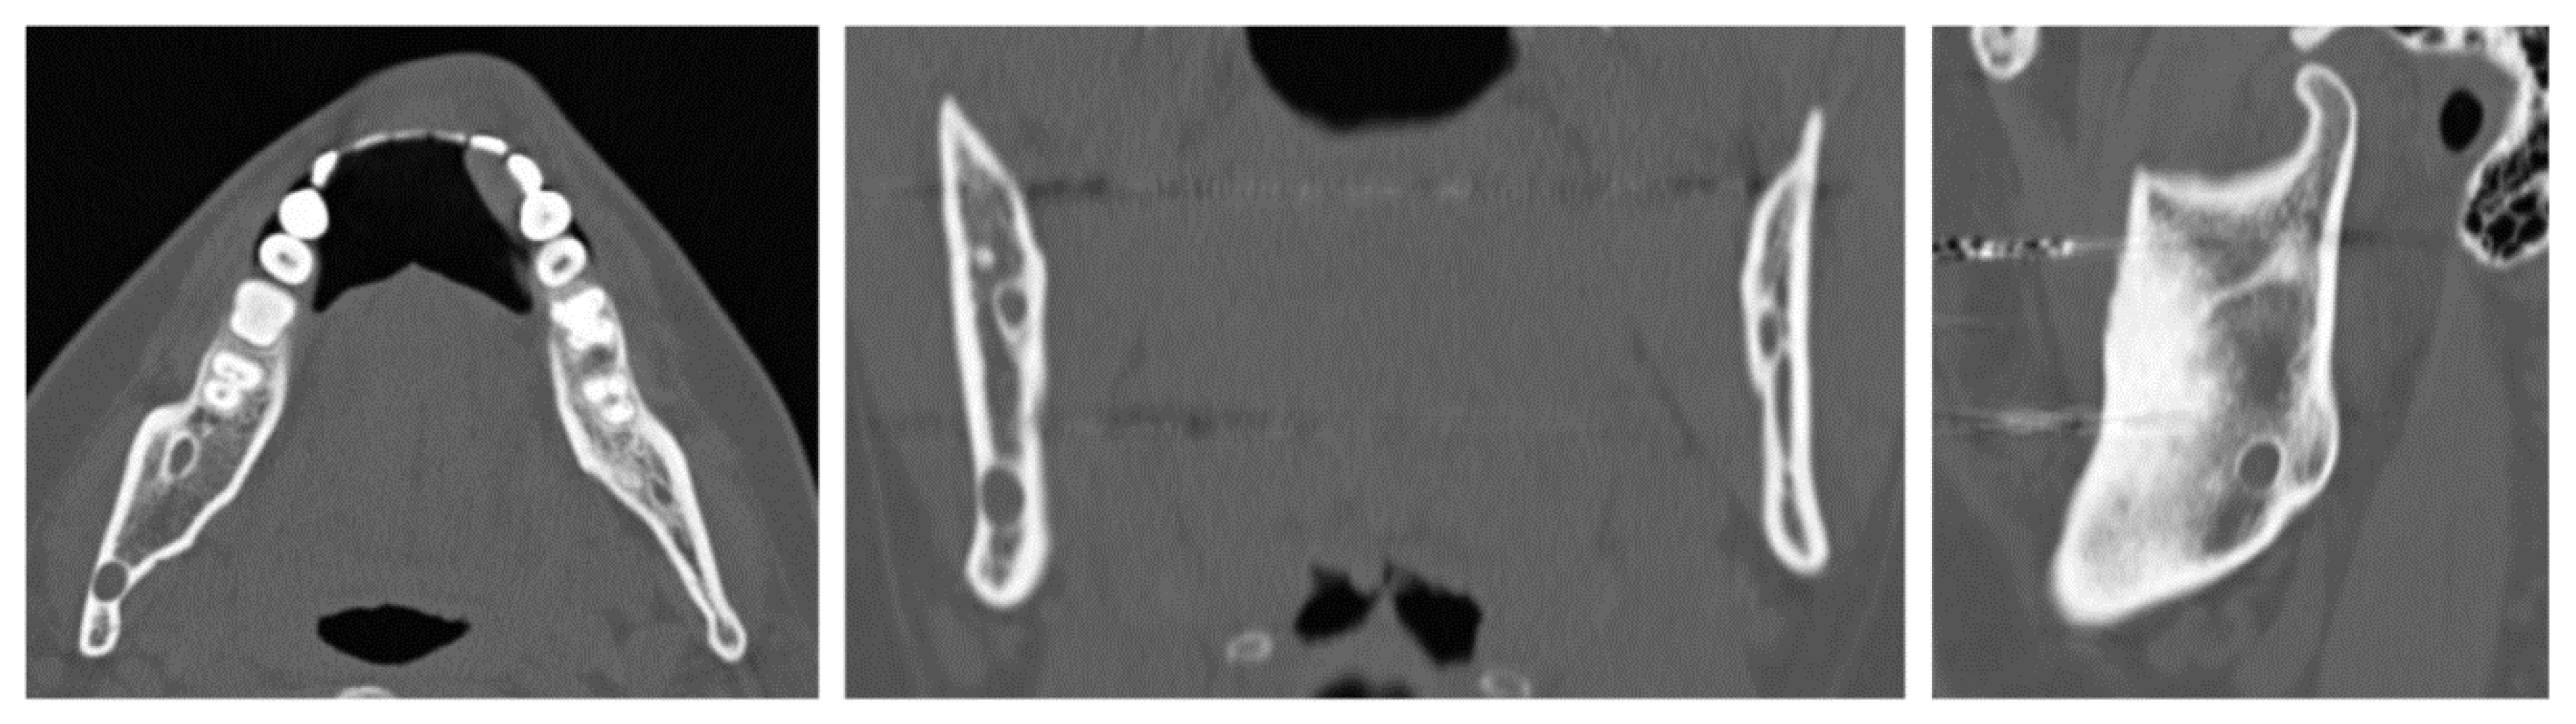

A 32-year-old patient came to our attention during an oncological follow-up, which included the execution of an OPT (Orthopantomography) X-ray, revealing a new osteolytic lesion at the right mandibular angle. In 1996, the patient underwent surgical removal of a unicystic ameloblastoma in a different hospital. We reviewed the patient’s most recent radiological documentation, which was an OPT X-ray taken 12 years earlier (8 years after the initial surgery) showing no mandibular lesions. A mandibular CT scan was requested to better define the lesion (Figure 12).

Figure 12.

Evidence on the mandibular CT scan of the appearance of a new osteolytic lesion, visible on axial, coronal, and sagittal views.